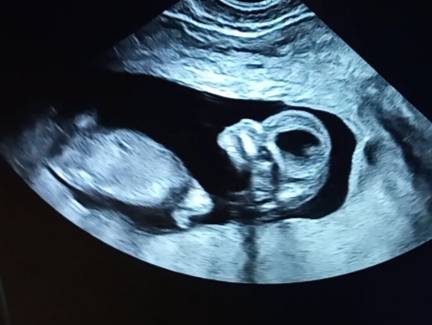

Сходила на первый скрининг. Думала, что иду в 11,5, а оказалось уже 12,3. Сказали, что девочка живет у нас и растет, но очень активная девочка. Дали поснимать как бултыхается. Спокойно лежать не стала, поэтому стопкадр приличный не получился ни у узиста, ни у меня